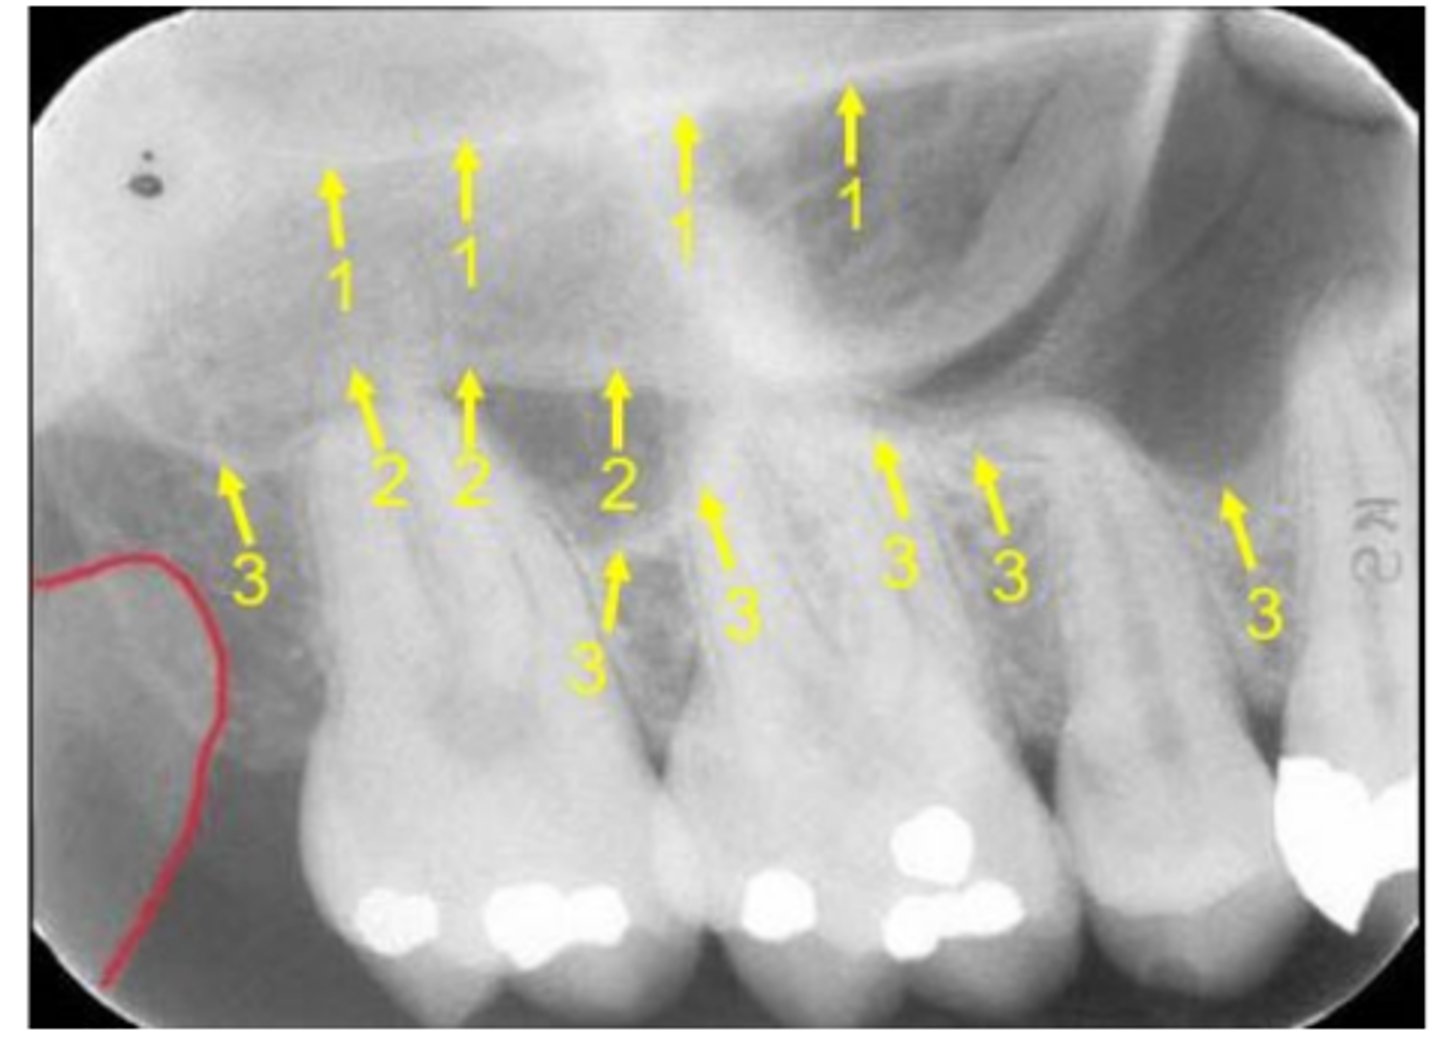

New cards

Name the line indicated by arrows labeled #2.

42

Name the elongated radiopacity indicated by #5.

43

Name the large radiopacity with a rounded inferior margin indicated by #4.

44

Name the horizontal radiopaque line labeled #2.

45

Name the curved line scalloping between tooth roots labeled #3.

46

Name the curved, conical structure outlined in the bottom left corner of the image.

47

Name the small, radiolucent dot indicated by #4.

48

Name the curved radiopacity, the superior border of which is labeled #7.

49

Name the curved, radiopaque structure indicated by the arrows.

50

Name the curved, radiopaque structure indicated by arrow #3.

64

Name the curved, hyperdense line that superimposes the roots of the teeth indicated by #7.

65

Name the line indicated by arrows labeled #1.

66

Name the two thin, curved, radiopaque lines that merge indicated by arrows #4.

<p>Name the two thin, curved, radiopaque lines that merge indicated by arrows #4.</p>